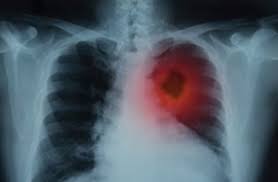

- 크거나 기도 근처에 위치한 경우 기침, 객혈, 호흡곤란, 흉통 등이 나타날 수 있음

- 흉부 X‑선 또는 흉부 CT로 발견

- 악성 결절인 경우 수술, 영상치료, 항암치료 등 치료 시행